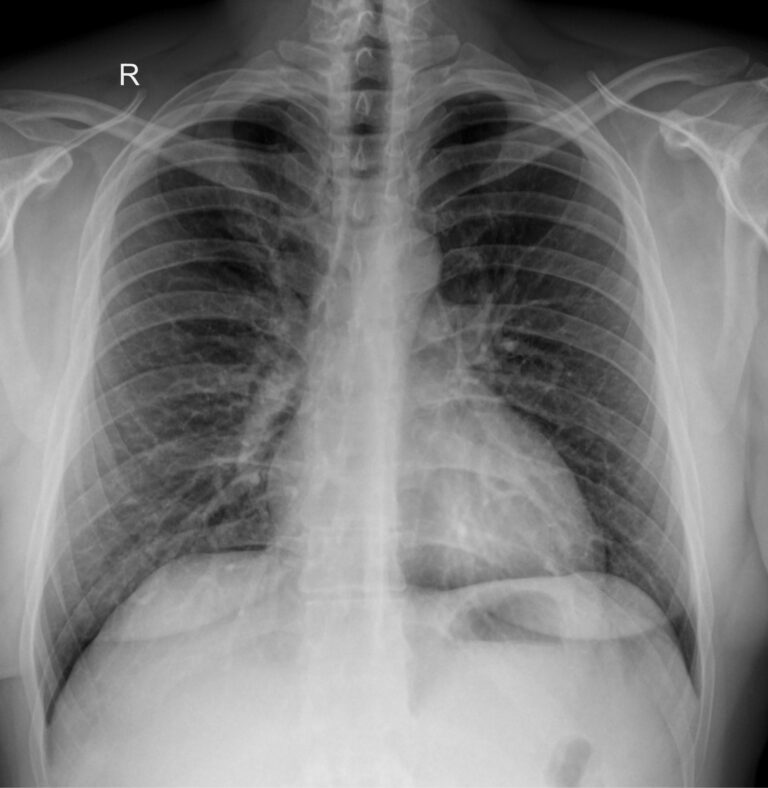

Диагностика с помощью рентгеновского излучения основана на его способности проходить сквозь живые и неживые объекты. В том числе, через тело человека. Органы разной плотности поглощают разное количество излучения, в результате на классическом негативном снимке наиболее плотные образования, кости, отображаются самыми светлыми, а наполненные воздухом ― почти черными. Мягкие ткани визуализируются как пятна серых оттенков. Участки, цвет и форма которых не типичны, говорят о патологии.

Снимок грудной клетки используют, чтобы получить изображение расположенных здесь органов: легких и дыхательных путей, контуров сердца с сосудами, а также позвоночника и костей. Обычно для диагноза достаточно одного снимка ― в прямой проекции, когда лучи идут сзади наперед. Иногда врач назначает снимок в боковой проекции, то есть слева или справа. Это необходимо, если требуется более точно определить сегмент поражения или достоверно исключить патологический процесс. Крайне редко требуются косые проекции, но они тоже бывают.

Что показывает рентген грудной клетки

На рентгенограмме видны следующие образования, расположенные в грудной клетке:

• Мягкие ткани: грудные мышцы, кожные складки;

• Костный скелет: ребра, ключицы, грудина, нечетко ― позвонки, в пожилом возрасте ― хрящи;

• Легочные поля: определяются их прозрачность, симметричность, легочный рисунок;

• Корни легких: топография, форма, структура, ширина;

• Средостение: положение сердца и сосудов, формирующих его дуги;

• Купол диафрагмы: четкость, местонахождение;

• Синусы: свободные или заполненные.